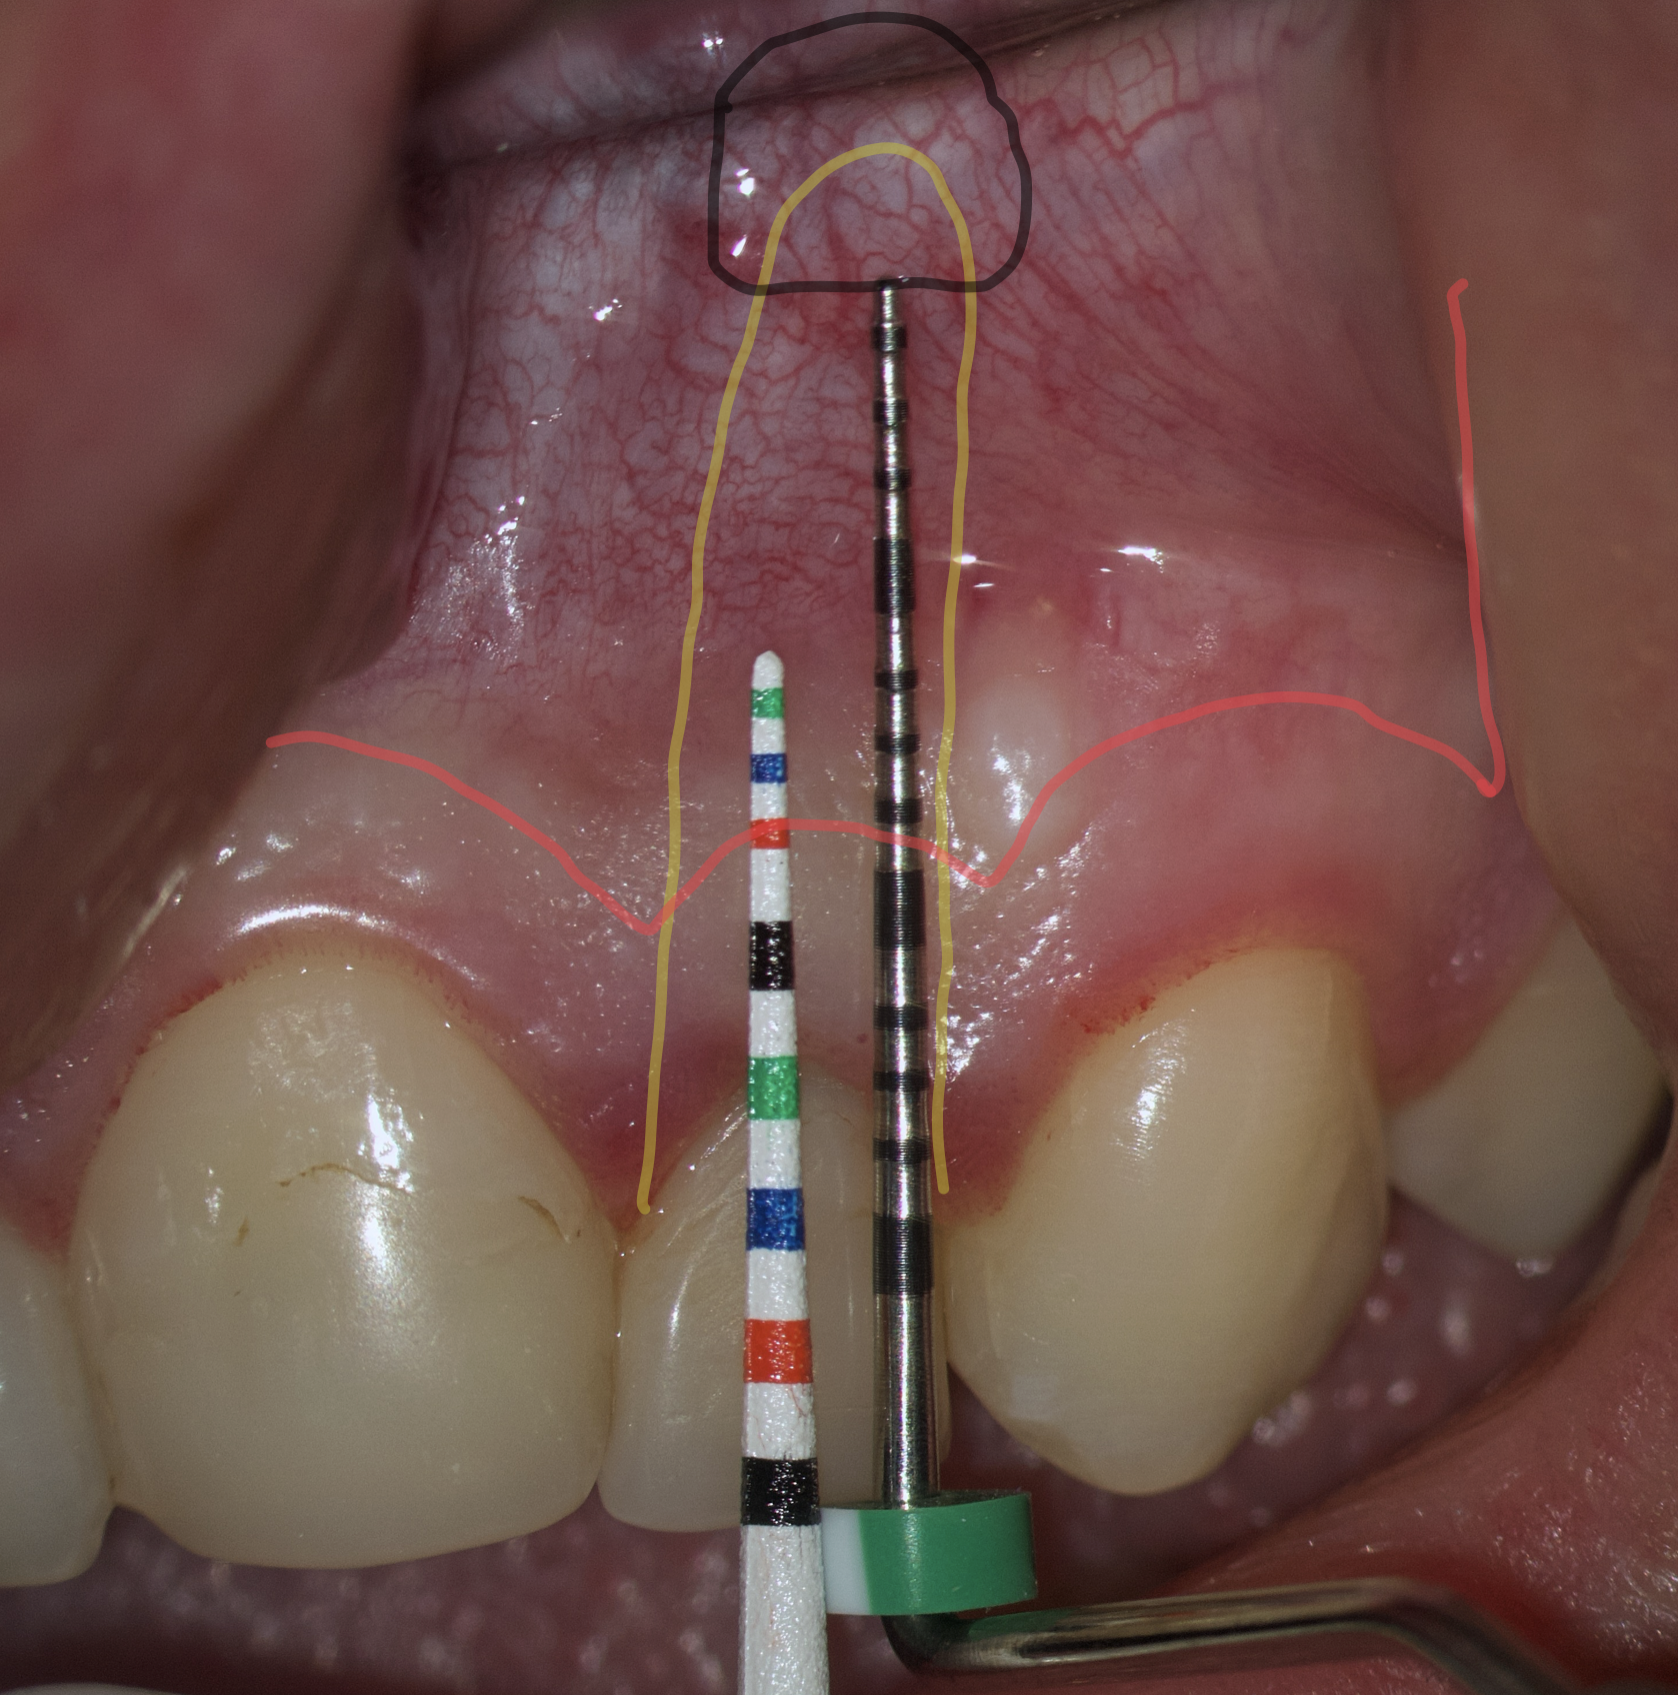

Therefore, the selection of this type of incision requires thorough treatment planning [12]. To avoid the incision falling into an existing bone defect or a defect created by an osteotomy, it is rational to plan a submarginal incision. We can determine whether we can make it, according to the clinical situation of a patient by following approach. To do this, first we need to determine on the CBCT where the bone defect is located or where the osteotomy will take place. Then, using a virtual ruler, measure the distance from the incisal edge of the tooth on which the intervention will be performed to the beginning of the bone defect or osteotomy (Fig 7).

We transfer this distance is transferred to a metal probe and fixed with an endodontic stopper. Next, we take a plastic probe and substitute it near the zenith of a tooth on which the intervention will be performed at a mark of 6 mm (3 mm must be retreated to perform a submarginal incision and another 3 mm is needed for the formed flap to overlap healthy bone tissue) (Fig 8).

We compare the lengths of the plastic and metal probes. The first option is when the metal probe is above the plastic one, then we can assure that the incision and the Ochsenbein-Luebke flap will accurately cover the bone defect and the submarginal incision is safe (Fig 9).

The second option is when the lengths of both probes are the same. This option is when a tooth has previously undergone root apex resection or a root is anatomically short or there is extensive periapical lesion. Under these conditions, we understand that there is still a safe distance of 3 mm so that the formed Ochsenbein-Luebke flap will also cover the bone defect and therefore, we can perform a submarginal incision and flap (Figs 10 and 11).

The third option is when the length of the metal probe is shorter than the plastic one. This option arises when the tooth has root resorption, root perforation or extensive periapical lesion extending to the alveolar crestal bone. In such conditions, performing a submarginal incision is contraindicated and it is preferable to use a papilla-base or intrasulcular incision (Figs 12 and 13).